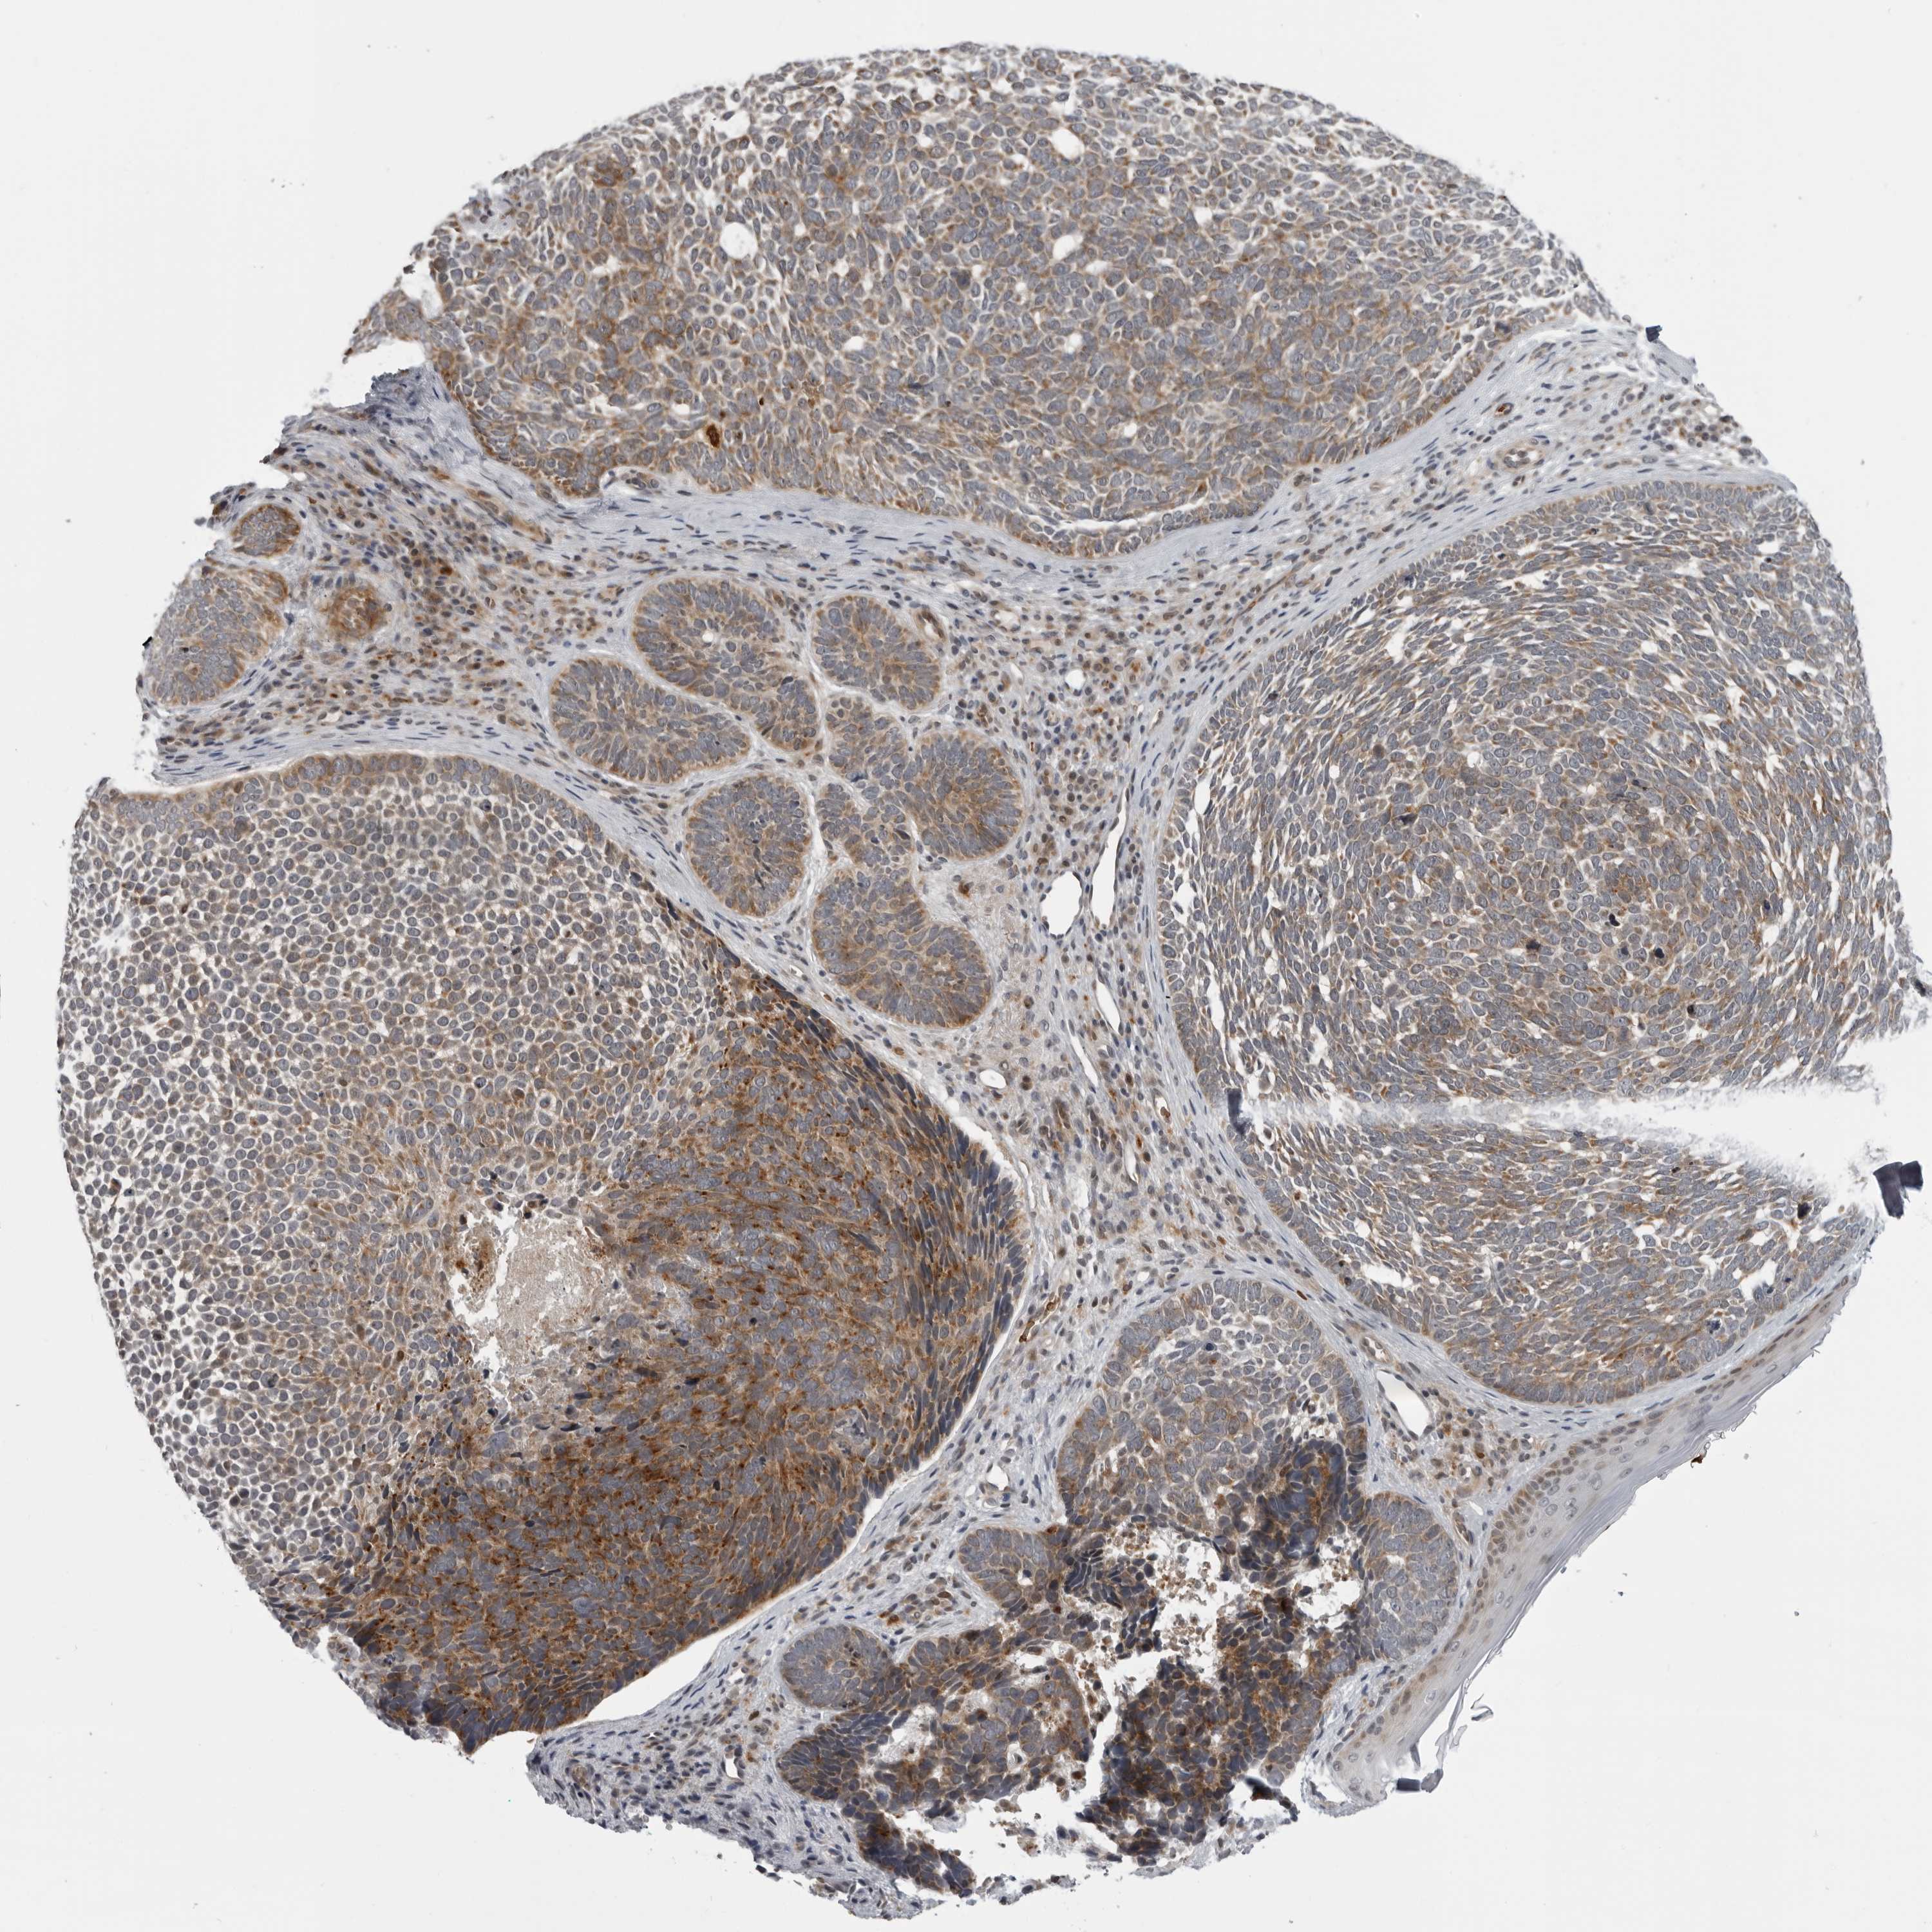

SKIN CANCER - Protein expressioni

A mouse-over function shows sample information and annotation data. Click on an image to view it in a full screen mode. Samples can be filtered based on level of antibody staining by selecting one or several of the following categories: high, medium, low and not detected. The assay and annotation is described here.

Antibody stainingi

Antibody staining in the annotated cell types in the current human tissue is reported as not detected, low, medium, or high, based on conventional immunohistochemistry profiling in selected tissues. This score is based on the combination of the staining intensity and fraction of stained cells.

Each image is clickable and will lead to virtual microscopy that enables deeper exploration of all samples and also displays staining intensity scores, fraction scores and subcellular localization as well as patient and tissue information for each sample.

Antibody CAB025497

Squamous cell carcinoma, NOS

Squamous cell carcinoma, metastatic, NOS